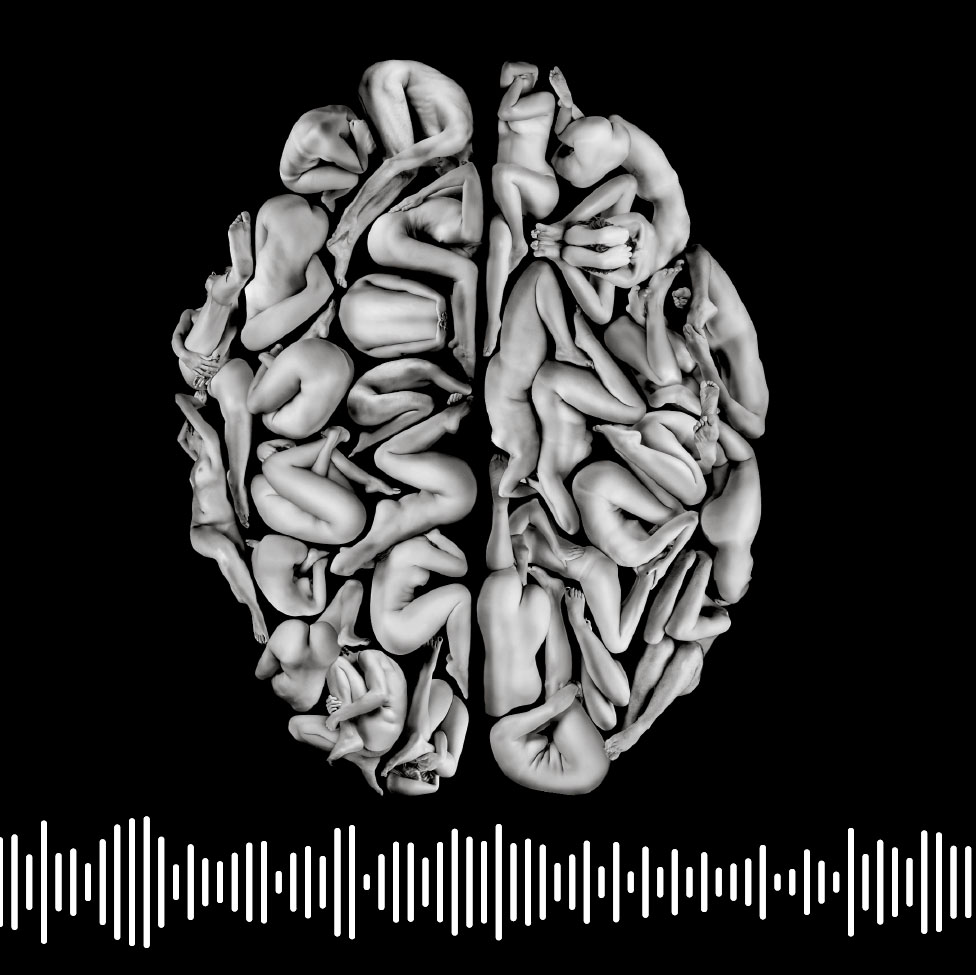

Descubre tu botón cerebral Las voces de XLSemanal Podcast | El punto 'je' de la felicidad (y cómo activarlo)

Investigadores de la Universidad Emory, en Atlanta (Estados Unidos), hallan el botón cerebral que dispara la felicidad. Su estudio ha conseguido demostrar que estimulando el haz del cíngulo, los pacientes sentían alegría y bienestar. Escucha cómo este descubrimiento podría ayudar a combatir la depresión y el dolor crónico en 5 minutos en el nuevo podcast de Las voces de XLSemanal.

Fue un hallazgo tan feliz como casual. Los neurocientíficos de Emory no buscaban el punto cerebral que dispara la risa, sino que trabajaban con pacientes de epilepsia para buscar la fuente neuronal de sus convulsiones. La sorpresa llegó cuando descubrieron que la estimulación eléctrica del haz del cíngulo les hacían sentirse muy alegres. Una de las pacientes incluso contó chistes de carrerilla tronchada de la risa.